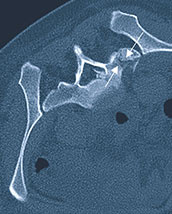

Kreuzbeinbruch vor Verschraubung.

Kreuzbeinbruch nach Verschraubung.